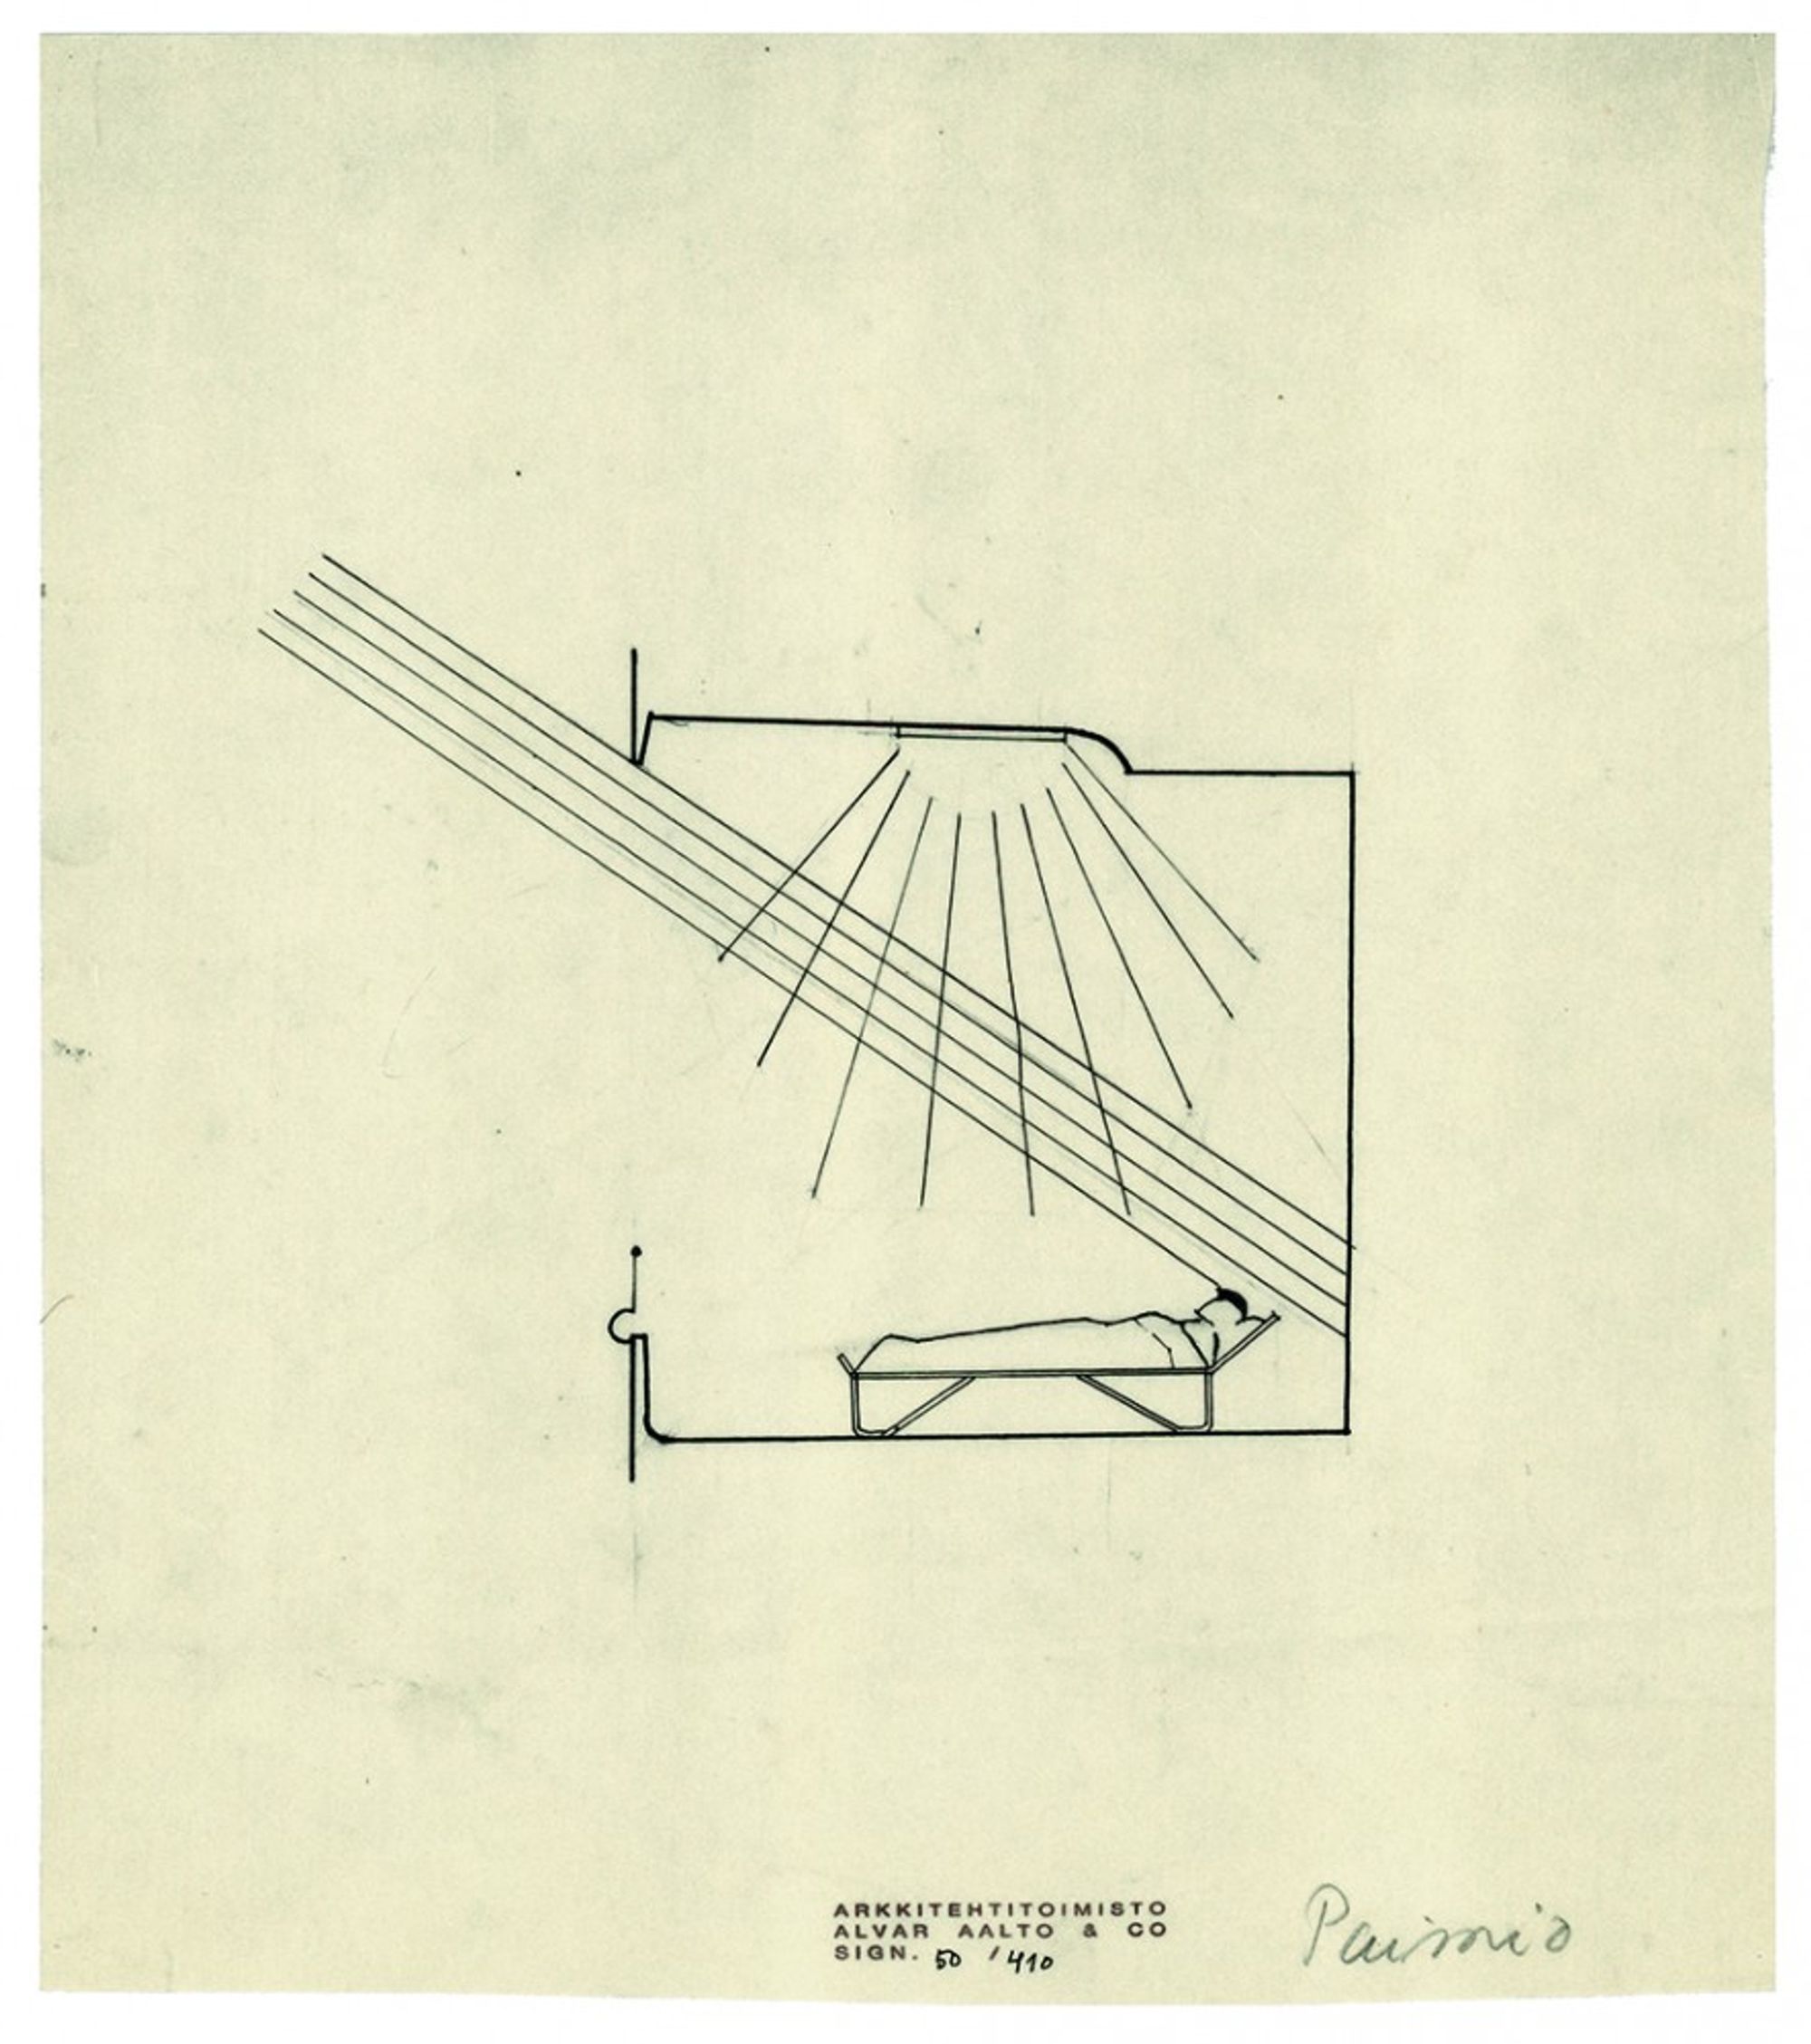

ARCHITECTURE AND ILLNESS: Beatriz Colomina On Tuberculosis, Modernism, and COVID-19